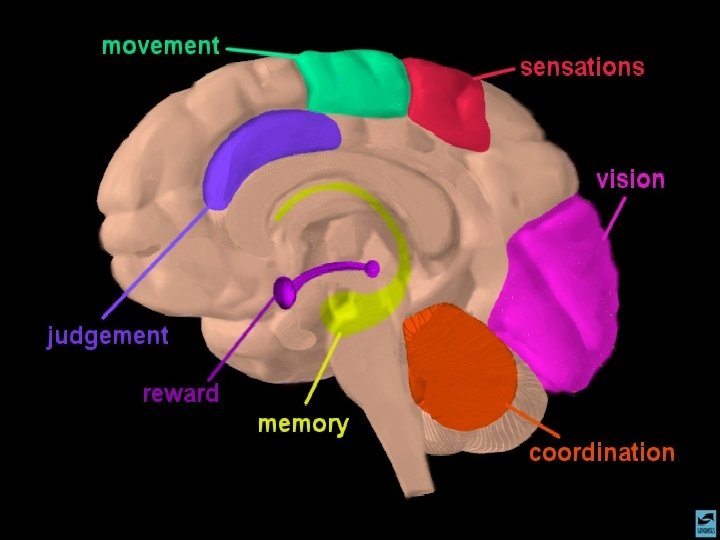

A AÇÃO DAS DROGAS NO SISTEMA NERVOSO CENTRAL O CÉREBRO

A AÇÃO DAS DROGAS NO SISTEMA NERVOSO CENTRAL O SISTEMA LÍMBICO

A AÇÃO DAS DROGAS NO SISTEMA NERVOSO CENTRAL OS NEUROTRANSMISSORES - NORADRENALINA - SEROTONINA - DOPAMINA - GABA - ACETILCOLINA

ANFETAMINAS E COCAÍNA EFEITOS CEREBRAIS: ATIVA OS SISTEMAS DOPAMINÉRGOS MESOLÍMBICOS E MESOCORTICAIS, INIBINDO A RECAPTAÇÃO DE DOPAMINA NOS TERMINAIS SINÁPTICOS E PROMOVENDO SUA LIBERAÇÃO NAS SINAPSES.

MACONHA TETRAHIDRO CANABINOL EFEITOS CEREBRAIS 1 - DISTRIBUI-SE RAPIDAMENTE POR TODO O CÉREBRO 2 - TEM AFINIDADE COM O RECEPTOR FORMADO AMANDAMIDA, QUE EXISTE NO HIPOCAMPO, TRONCO CEREBRAL E TRATO PÁLIDO 3 - AGE COMO NEUROMODULADOR ALTERANDO A PRODUÇÃO DE UM SEGUNDO MENSAGEIRO REGULADO POR OUTRO NEUROTRANSMISSOR

ALUCINÓGENOS (LSD, MESCALINA, PSCILOBICINA, ETC. ) EFEITOS CEREBRAIS INTERAGEM COM RECEPTORES DE SEROTONINA DE FORMA COMPLEXA EM TÁLAMO E CÓRTEX CEREBRAL

OS OPIÁCIOS EFEITOS CEREBRAIS OS OPIÁCIOS LIGAM-SE AOS RECEPTORES CEREBRAIS DE ENDORFINAS